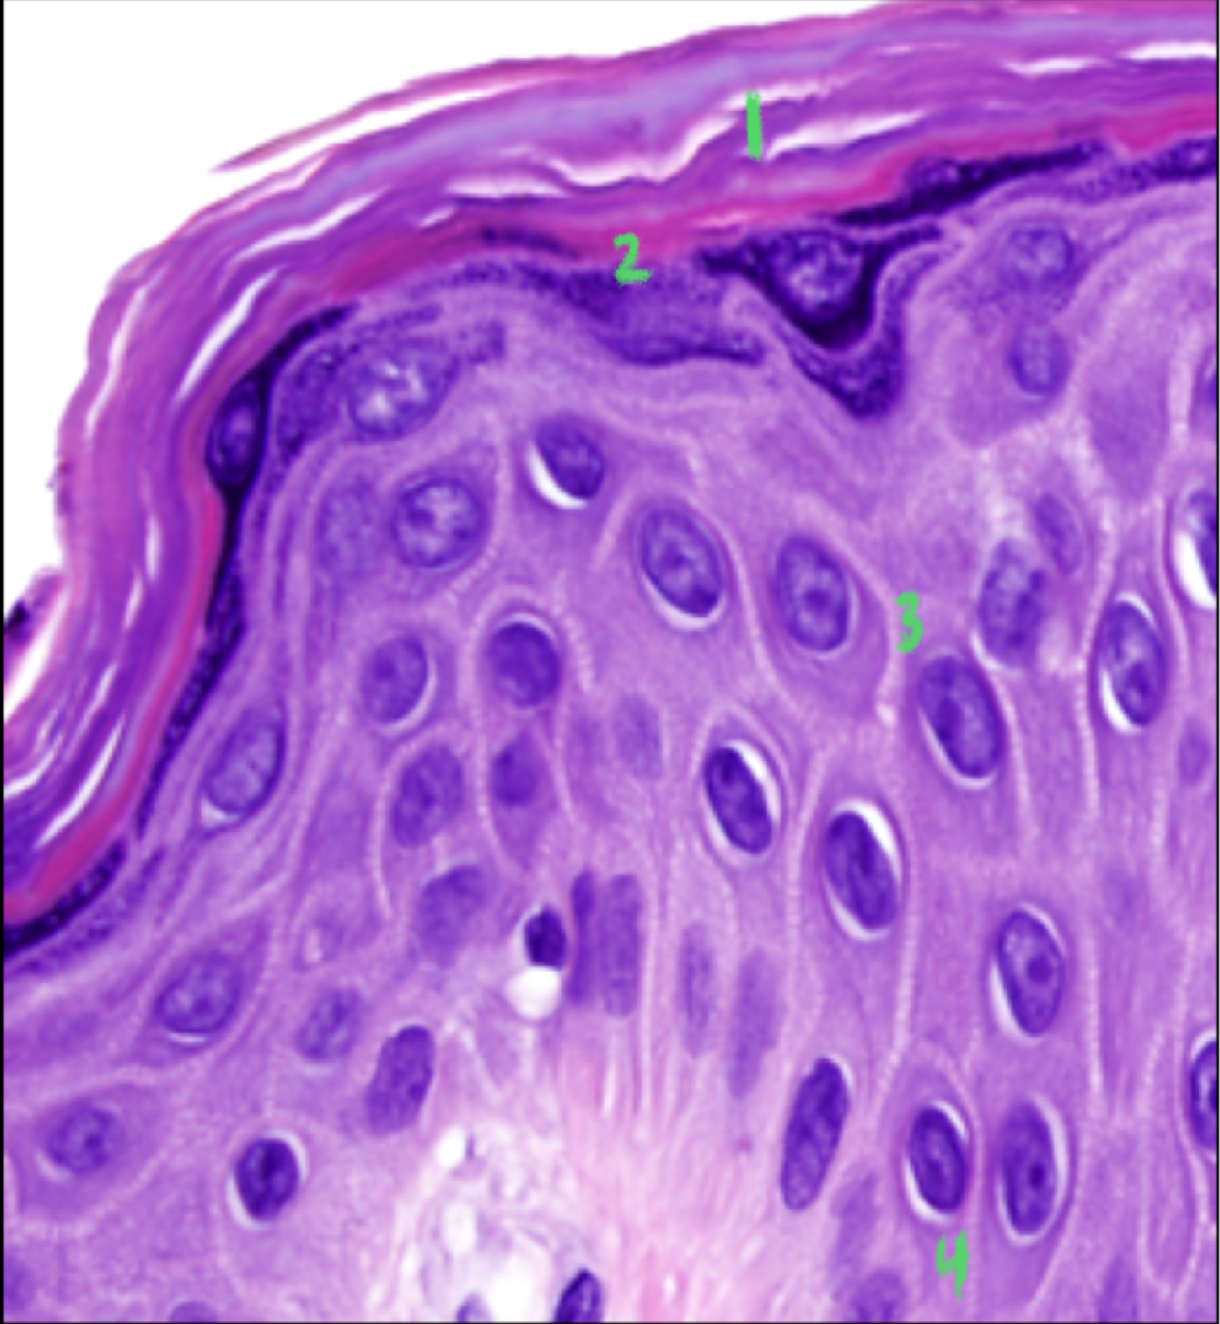

What are the four layers of the keratinocytes and what is the function of each?